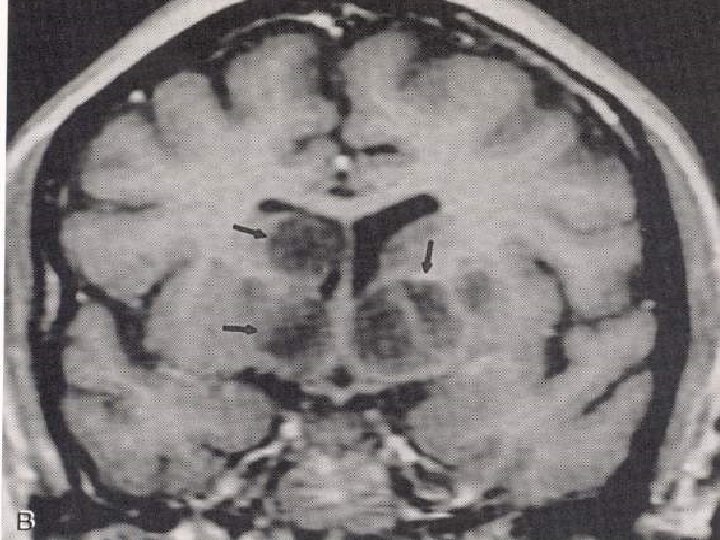

Tüberkülomlar n n İntrensek beyin kitleleri CPA’da, sellar bölgede, kavernöz sinüste, durada da tüberkülomlar tanımlanmıştır. BT’de her türlü lezyonu taklit edebilir. Genellikle izodens kitlelerdir. Çevresel veya homojen kontrast tutarlar. MR’da ise T 1’de hipo veya izointens olup kontrasttan sonra çok iyi boyanırlar. Çok sayıda, yaygın, küçük lezyonlar olarak veya matür tüberkülomlar şeklinde, daha büyük, ortası nekrotik hipointens, çevresi ödemli lezyonlar şeklinde karşımıza çıkabilirler.